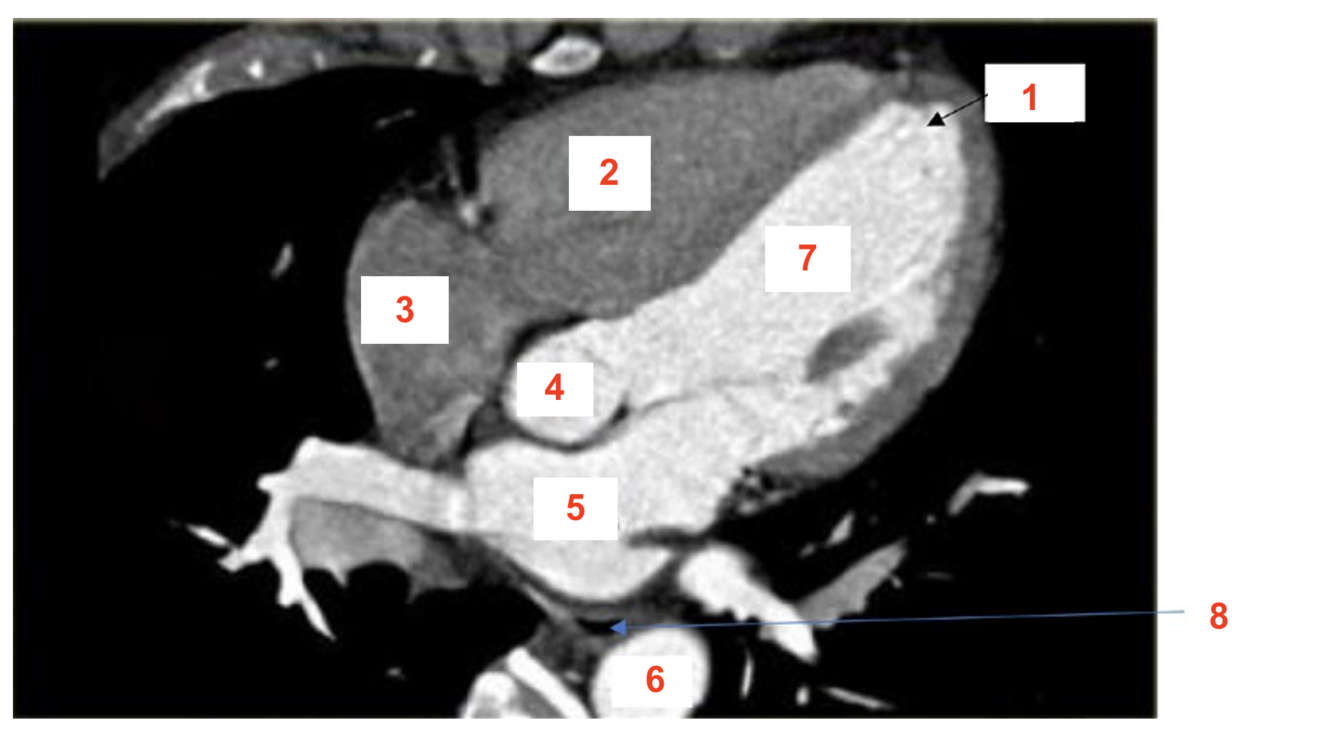

14

label 1

RV

15

2

Apex

16

3

RA

17

4

LV

18

5

oesophagus

19

6

LA

20

7

aorta

21

8

azygos vein